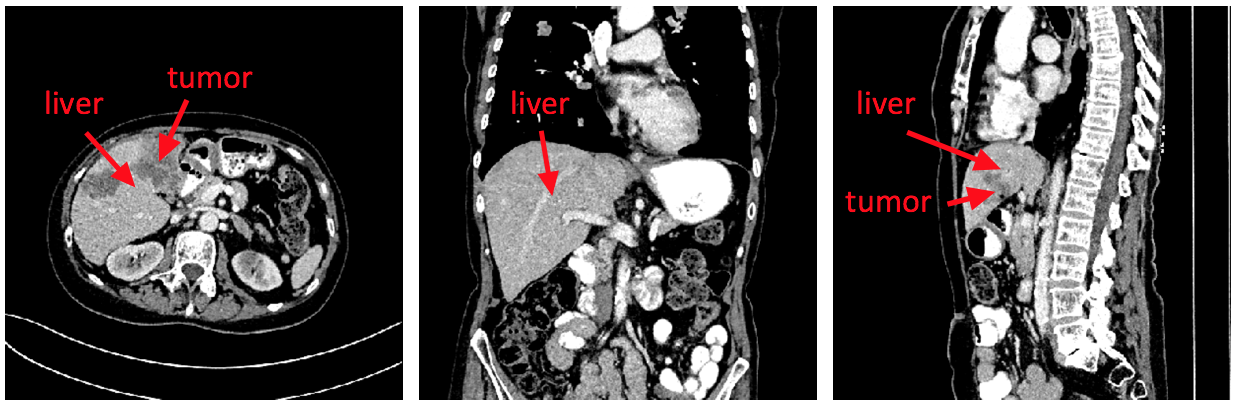

Zhenggang Wang, and Guanling Wang. Triplanar Convolutional Neural Network for Automatic Liver and Tumor Image Segmentation [J]. Int J Performability Eng, 2018, 14(12): 3151-3158.